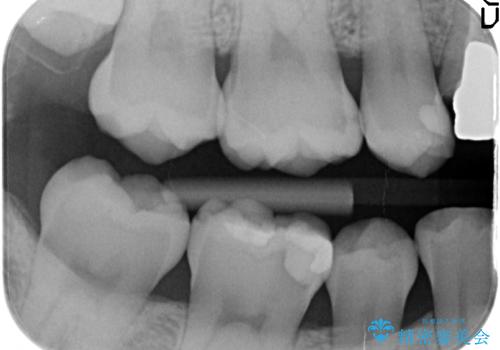

- 右下6番目の歯がしみるといらっしゃった方の症例です。

古い樹脂及び虫歯を除去後、セラミックインレーにて修復を行いました。

虫歯治療は虫歯の進行度によって処置が変わってきます。

虫歯が小さければ、インレー・クラウン等による修復・補綴処置を行うだけで済みます。

しかし虫歯が大きくなると神経処置や抜歯等をしなければならない場合もあります。